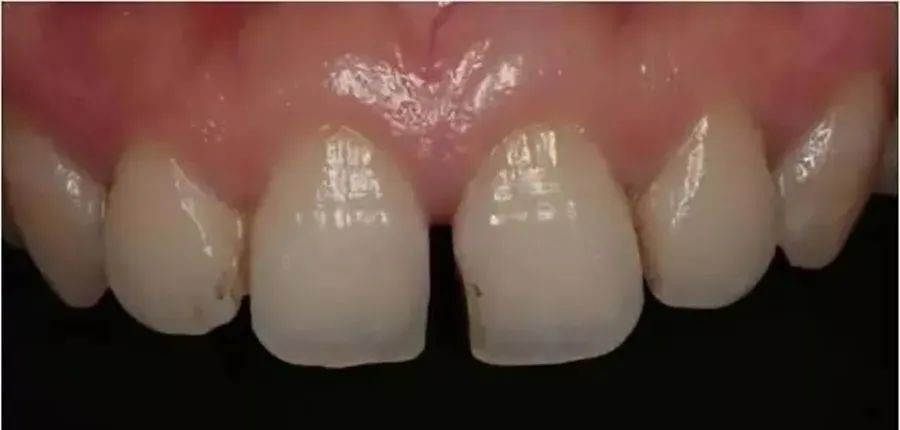

2、感觉牙缝越来越大:感觉牙缝越来越大是由于牙周病造成,牙龈和下方牙槽骨的退缩,引起牙间本应由牙龈和牙槽骨占据的空间暴露出来,使患者感觉牙缝越来越大。